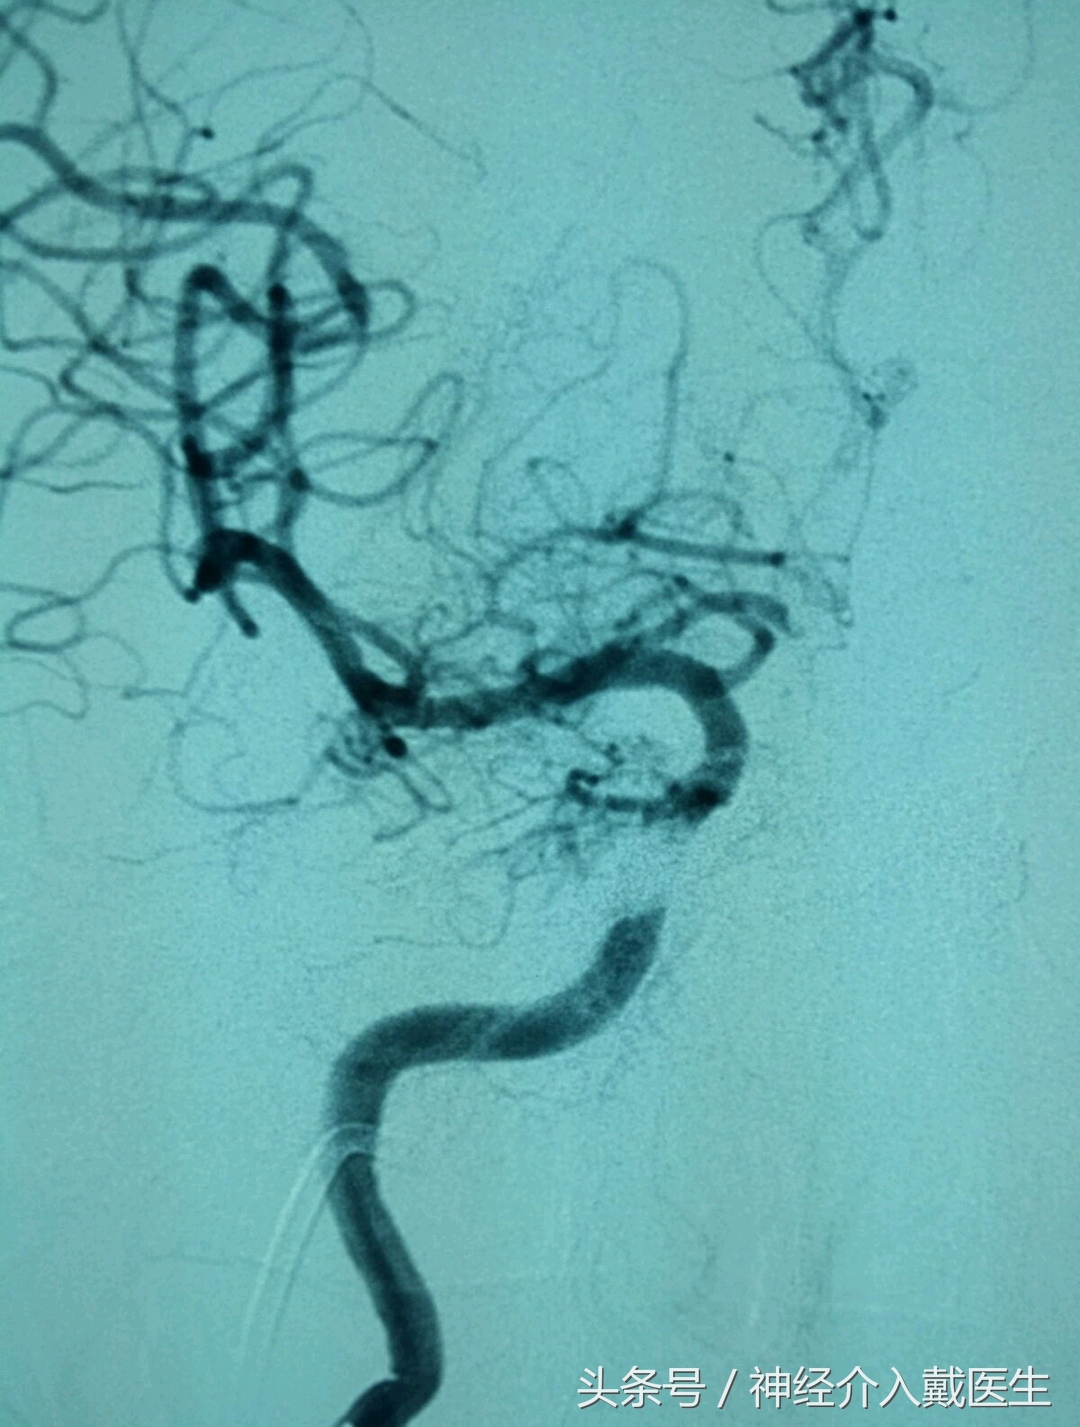

手术后效果正位像。